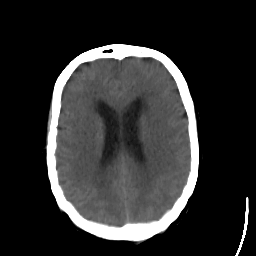

Stroke CT #1 -- Slice #16

[Home][Help][Clinical] Slice 16